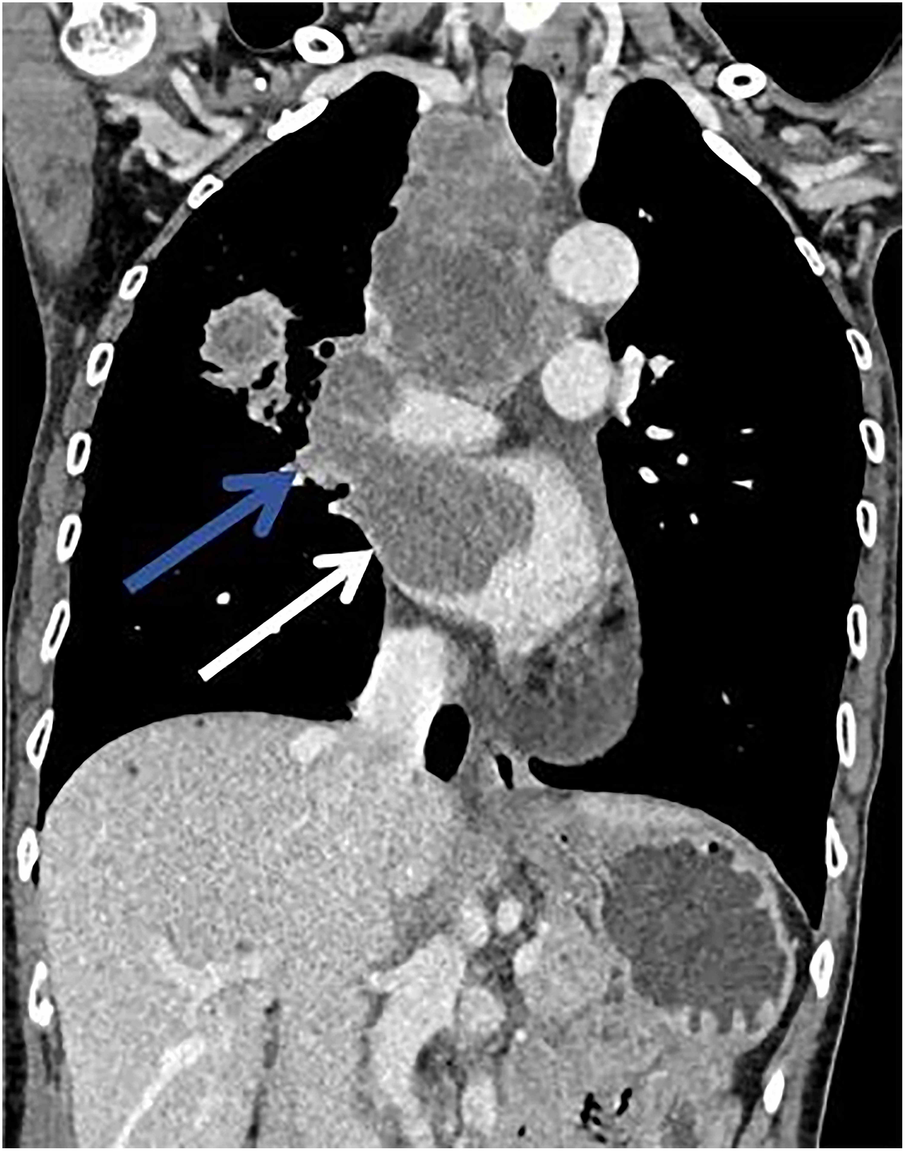

A 62-year-old non-smoking female presented to our hospital with kidney stones and underwent a comprehensive full-body examination. She self-reported being previously healthy and not experiencing any symptoms, except for a significant recent weight loss. During the physical examination, the patient appeared to be in good overall condition, with a blood pressure reading of 92/51 mmHg, a heart rate of 81 beats per min, a respiratory rate of 19 breaths per min, and no murmurs detected upon cardiopulmonary auscultation. The chest CT scan revealed lung cancer in the upper lobe of the right lung, which was further complicated by hilar and mediastinal lymph node metastasis. The lymphatic vessels surrounding the tumor appeared thickened and nodulated. Transthoracic echocardiography and organ acoustic imaging identified a 5.1 × 3.4 cm metastatic hypoechoic mass in the left atrium, closely associated with the right pulmonary vein (Figure 1). She underwent additional CT contrast imaging of the neck, chest, and upper abdomen, which confirmed the presence of a mass in the left atrium connected to the right upper pulmonary vein (Figure 2). Furthermore, a metastatic nodule was detected in the right adrenal gland. Simultaneously, a contrast-enhanced MRI of the head revealed a circular enhancing nodule located centrally within an oval lesion on the left side, indicative of skull metastasis. To elucidate the pathology, the patient ultimately opted for lung biopsy and immunohistochemical examination, which confirmed the diagnosis of non-small-cell lung cancer (NSCLC). Microscopic examination revealed cancer cells arranged in nests and clusters, demonstrating infiltrative growth, notable heterogeneity among the cancer cells, and proliferation of interstitial fibrous tissue (Figure 3). Following antigen retrieval, blocking, antibody staining, and color development steps in immunohistochemistry, the results indicate that the cancer cells exhibited positivity for CK, focal positivity for CK7, TTF1 (localized), and PD-L1 22C3 TPS (localized), with a Ki-67 proliferation index of approximately 20%. The cells tested negative for NapsinA, P40, P63, CK5/6, and ALK-D5F3. Special stains indicated negative staining for mucus carmine and positive staining for individual cells of AB-PAS.

Figure 2

There was a mild enhancement filling defect noted in the right upper pulmonary vein (blue arrow) and the left atrium (white arrow).